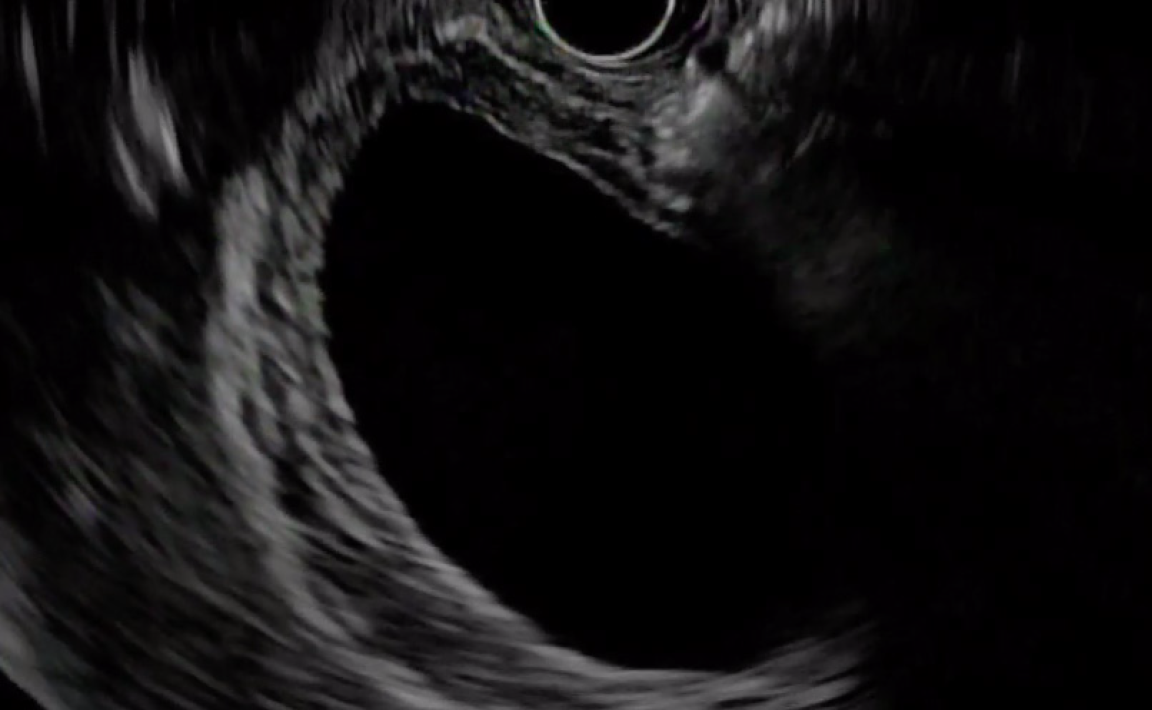

Figure 3 Endoscopic.

A: View of proximal flange of lumen apposing metal-stents deployed in duodenum with subsequent bile flow through stent; B: View of controlled radial expansion balloon dilatation of lumen apposing metal-stents to facilitate access to gallbladder lumen.